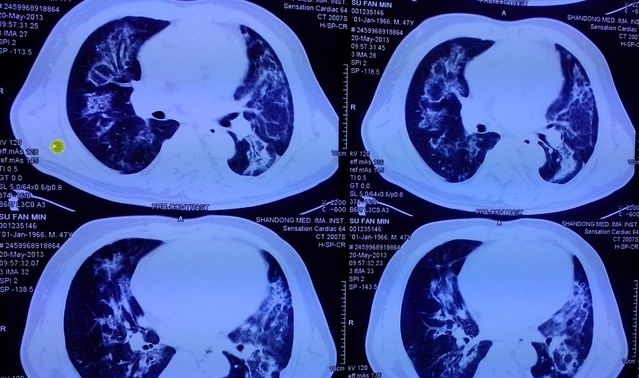

●在影像学上,尿毒症肺最典型的胸片则表现为“双侧肺野蝶翼状或蝙蝠状的渗出影”,说白了也就是以我们的肺门为中心,形成如蝶形或蝙蝠样阴影,如下图。我们大体上可将它的影像特点划分为5期,即肺泡性肺水肿期、肺淤血期、间质性肺水肿期、肺间质纤维化期和心脏扩大期。

尿毒症肺,影像中显著的渗出影